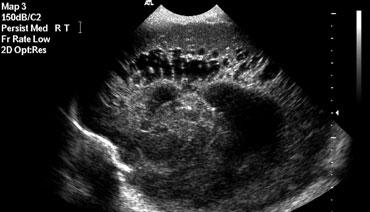

Xuất huyết nội sọ độ 3

Hình bên trái là xuất huyết nội sọ độ 3 lấp đầy não thất bên trái.

Cũng lưu ý vùng tăng âm hình nêm ở phía trên-bên của não thất.

Đây là hình ảnh của một ổ nhồi máu tĩnh mạch nhỏ.

Cùng bệnh nhân như trên.

Hai tuần sau, ổ nhồi máu tĩnh mạch đã tiến triển thành vùng giảm âm với sự hình thành nang.